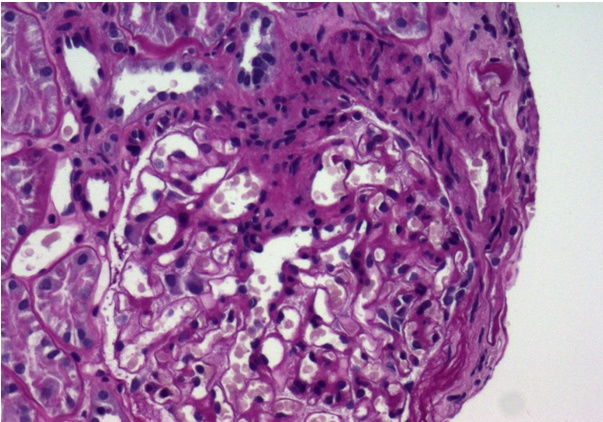

(그림 1)48세 남자 환자가 소변검사 및 혈압은 정상이었지만 여과율이 65ml/min으로 저하돼 시행한 신장조직검사상 사구체의 60%정도가 경화된 IgA 신장염4기로 판명됐다.